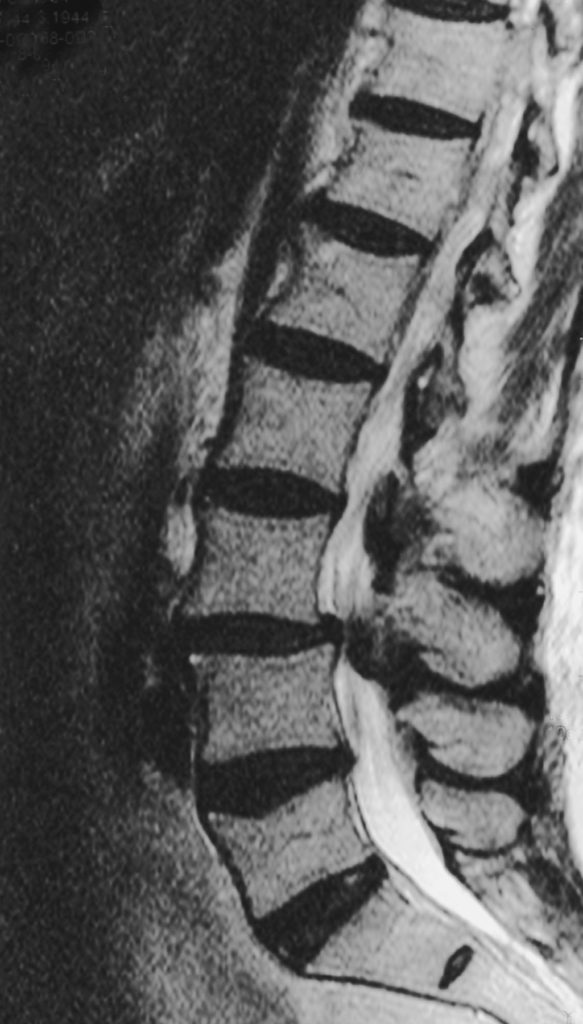

In meiner Praxis setze ich bei der Spinalkanalstenose-OP das mikrochirurgische Verfahren ein. Über einen kleinen Hautschnitt verschaffe ich mir Zugang zu dem Bereich der Wirbelsäule, in dem die Verengung liegt. Unter dem Operationsmikroskop vergrößere ich die betroffenen Strukturen stark und arbeite dadurch besonders präzise.

Im Rahmen dieser sogenannten mikrochirurgischen Dekompression entferne ich kleine Knochenanteile oder verdickte Bänder, die auf Nerven oder Rückenmark drücken. So erweitere ich den Wirbelkanal und stelle den Platz für die Nerven wieder her.

Das Ziel der Operation liegt darin, die Ursachen der Einengung so gezielt wie möglich zu beseitigen. So können Schmerzen und neurologische Ausfälle gelindert werden, während die natürliche Beweglichkeit bewahrt wird.